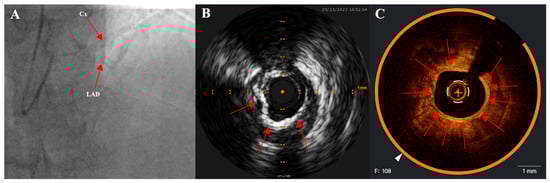

2.2. Coronary Angiography

2.3. Intravascular Imaging: IVUS (Intravascular Ultrasound) and OCT (Optical Coherence Tomography)